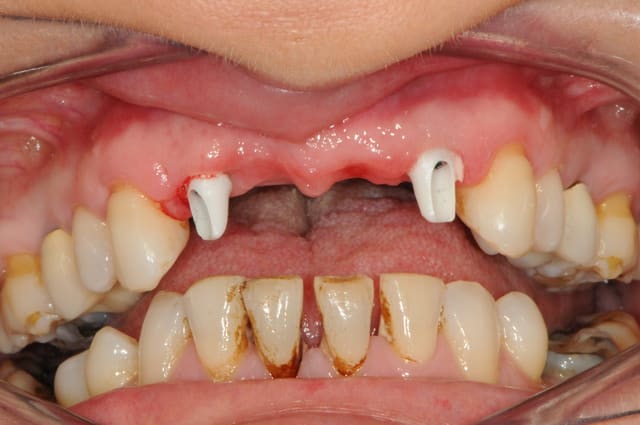

patiente 43 ans, très souriante, rigole tous le temps, fumeuse devant l'Eternel (1paquet/jour).

la parodontite et la mobilité sur 12 l'inquiète d'autan plus que les dents sont de plus en plus mobiles.

la 12 est perdue, mais également la 11 qui subit déjà une forte résorption gingivale.

21 et 22 pas beaucoup mieux.

on décide donc d'extraire 12-11-21-22, ROG, implantation et mise en charge immédiate. puis, chirurgie parodontal d'augmentation (surtout pour le secteur 11) et enfin bridge définitif avec chape en zircone. la patiente refuse catégoriquement une prothèse adjointe. elle est coquette

heureusement pour nous, car elle est toujours très souriante, elle ne découvre pas.